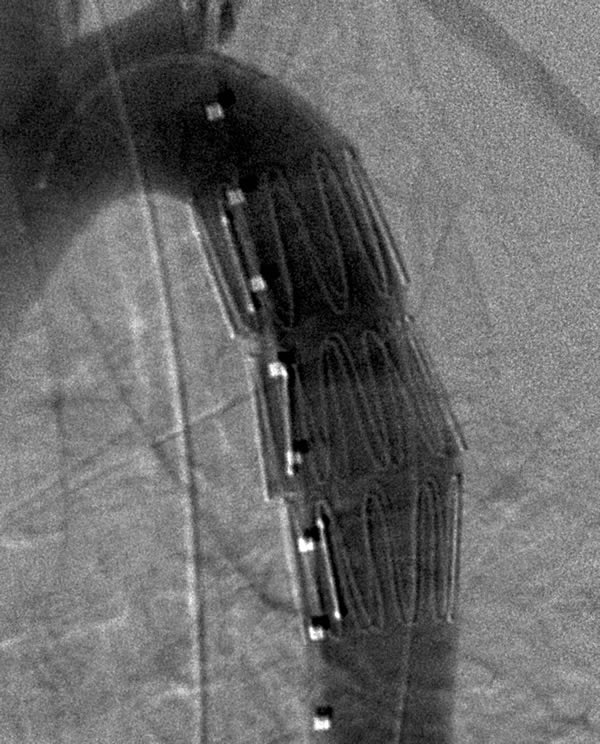

The modified original delivery sheath is then inserted snuggly into the hub of the long 16- or 18-French sheath over the guidewire. The endograft is transferred into the new sheath by advancing the delivery catheter while ensuring that the end of the original sheath is tightly nested in the receiving sheath. The original delivery system is then removed over the guidewire. The blunt back end of the dilator from the new sheath is inserted over the guidewire and used to push the endograft to the end of the long delivery sheath. The 5-French pigtail catheter is re-advanced into the distal aortic arch and control angiograms are obtained through the 5-French pigtail catheter prior to deployment of the endograft (Figure 3A). The endograft is deployed by withdrawing the sheath while maintaining the endograft in a fixed position with the pusher catheter. Angiograms are obtained through the 5 French pigtail catheter before and after gentle inflation of appropriate sized angioplasty balloons within the endografts (Figure 3B).